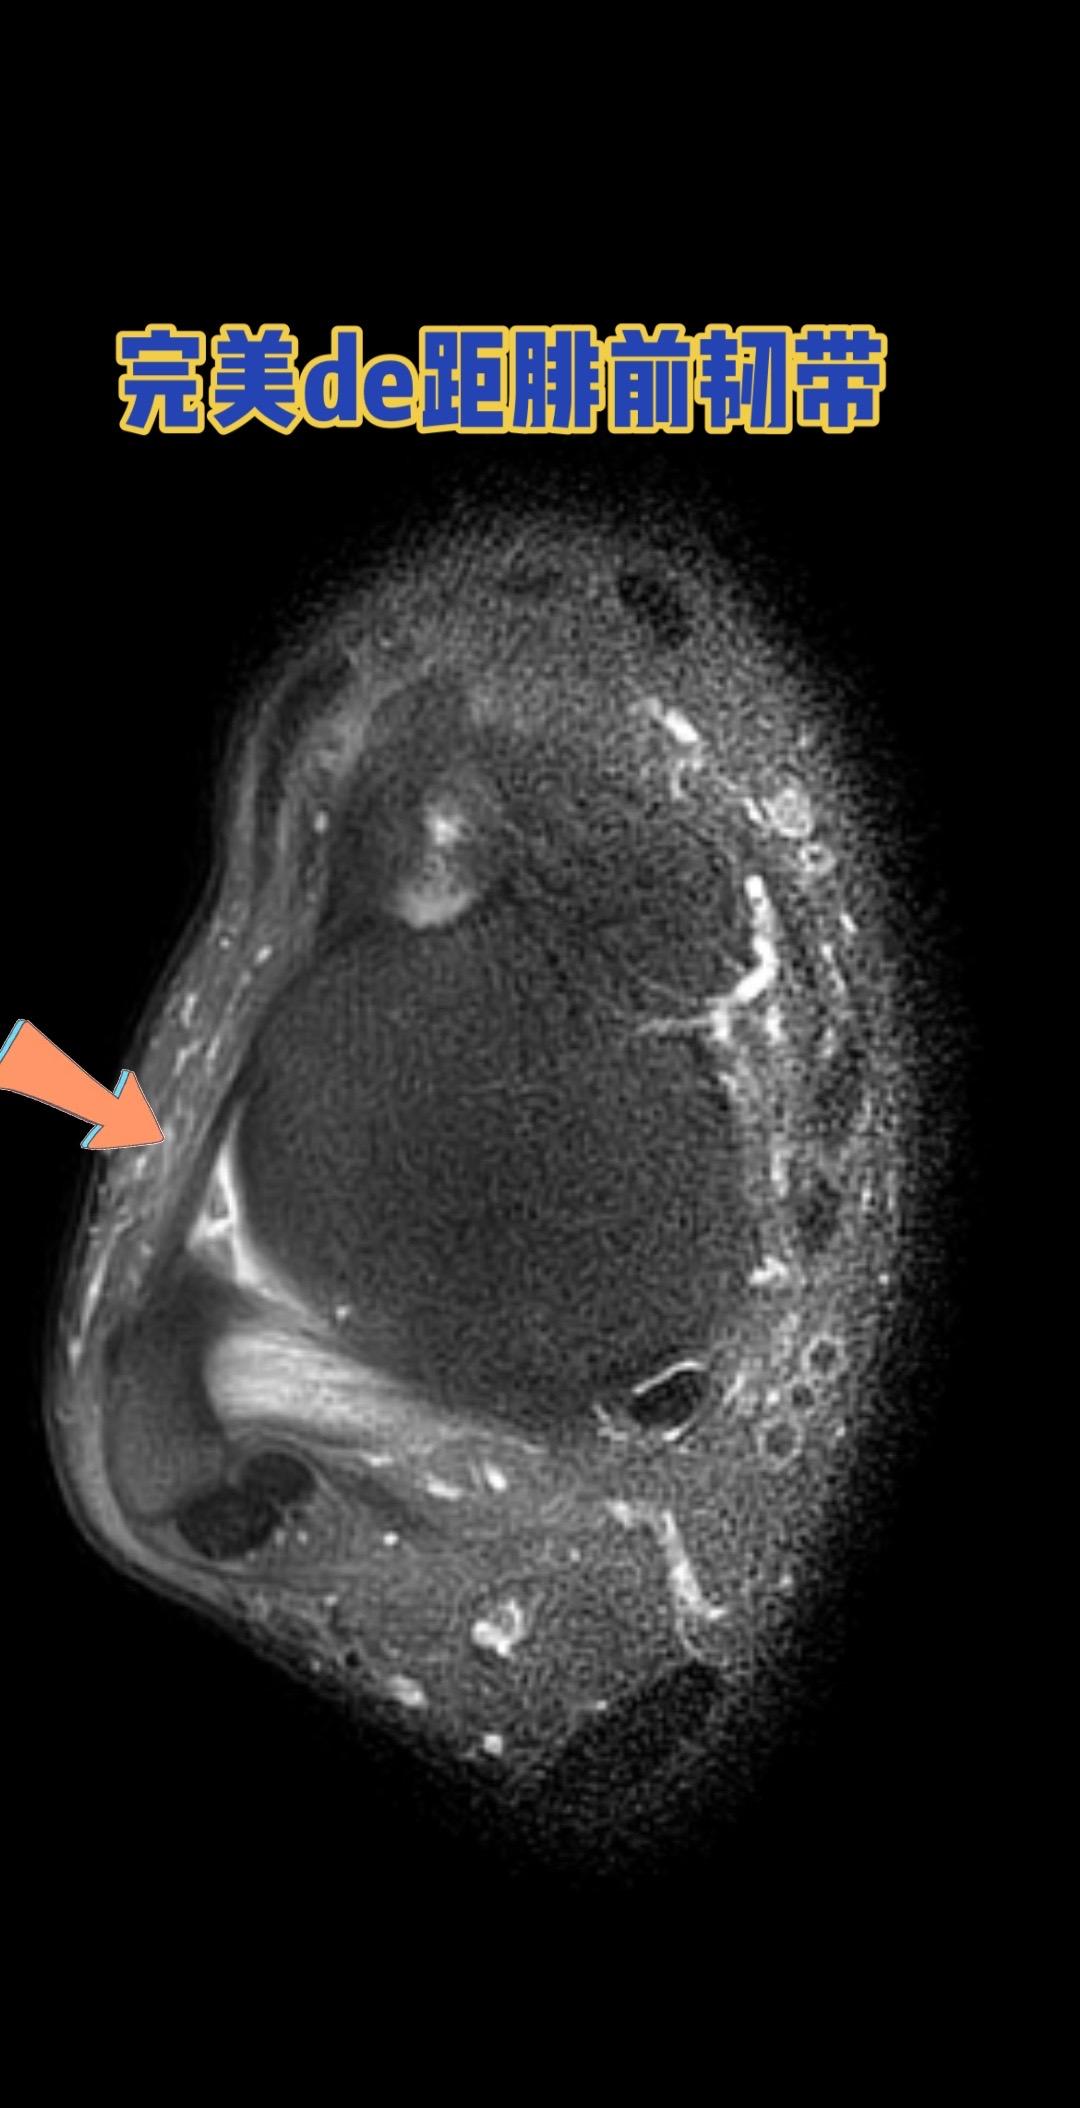

距腓前韧带。👉 健康的距腓前韧带长这样! 距腓前韧带

距腓前韧带。👉 健康的距腓前韧带长这样!